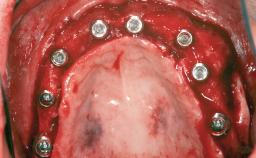

Iliac and Calvarial Bone Blocks for Onlay Grafting of a Severely Resorbed Edentulous Maxilla

A 45-year-old woman with a completely edentulous maxilla was referred to evaluate the possibility of rehabilitation with an implant-supported prosthesis. This patient was healthy and a non-smoker. She had been wearing a maxillary complete denture opposing a natural mandibular dentition since her twenties. This situation had resulted in progressive resorption of the alveolar ridge, repeatedly creating a need for relining the denture. Twenty years later, despite multiple adaptations and the use of “glues” the denture was unstable and causing the patient psychological and functional discomfort.

# of Implants 8

Type of Implants Reduced-Diameter|Two-Piece

Bone Augmentation Horizontal|Sinus Floor Elevation|Staged|Vertical

Augmentation Materials Autogenous chips|Autogenous block(s)